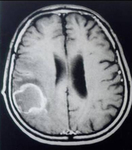

MRI brain in a patient with AIDS and reactivation of Chagas disease in CNS

Grupo de Estudos em Doenca de Chagas (GEDoCH), Departamento de Clínica Médica, Faculdade de Ciências Médicas, Universidade Estadual de Campinas, Sao Paulo, Brazil; used with permission